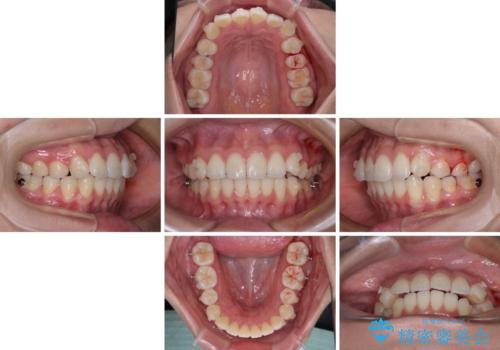

- 前歯のデコボコを治したいとのことで来院された患者様です。

上下顎ともに歯列全体の後方移動とIPR(歯と歯の間を削る)によってデコボコが解消するように設計し、インビザラインにより治療を行うこととしました。